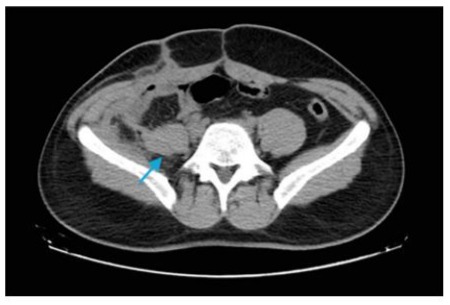

Figure 2: Post-surgical tomography, showing no cystic image. (indicated by the blue arrow).

On March 8, 2024, a follow-up CT scan (Figure 2) showed a reduction in the multiloculated collection or abscess in the right iliac muscle and fossa, measuring approximately 6.4 x 4.7 x 2.6 cm, compared to previous measurements of 7.6 x 4.4 x 2.5 cm. Finally, on April 11, 2024, resolution of the collection in the right iliac muscle was observed, with only residual soft tissue densification remaining in the lower right quadrant of the abdominal cavity, consistent with residual changes or those related to prior surgical manipulation. The patient had a favorable clinical outcome after the diagnosis, with resolution of pain and progressive reduction in the tomographic findings, continuing follow-up with the infectious disease team.